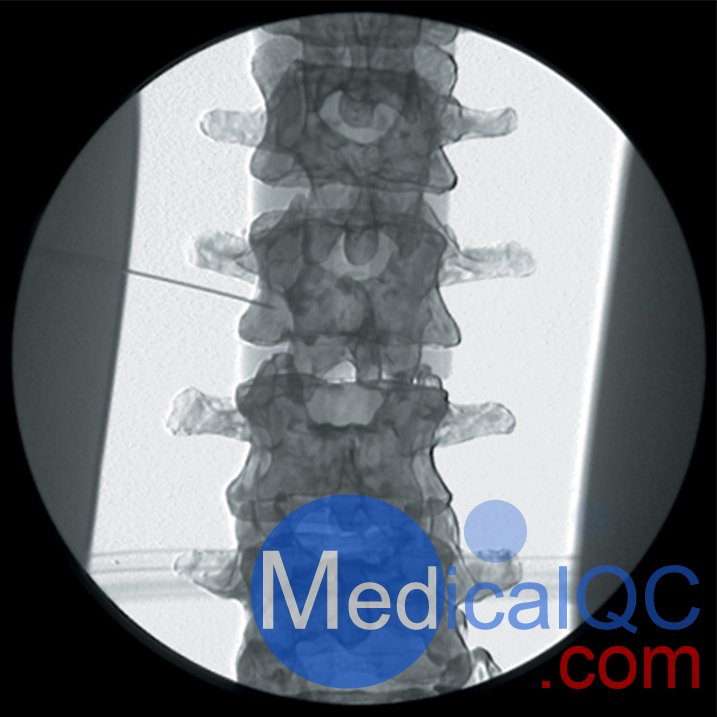

AR351脊椎穿刺模體,Adam,Rouilly脊椎穿刺模體是區(qū)域麻醉模擬人體模型,由曼徹斯特和索爾福德疼痛中心的顧問麻醉師設(shè)計的,用于培訓(xùn)麻醉師正確放置神經(jīng)塊中的針頭以進(jìn)行疼痛處理。

AR351脊椎穿刺模體,Adam,Rouilly脊椎穿刺模體可用于訓(xùn)練以下項目:

腰交感神經(jīng)阻滯

內(nèi)臟神經(jīng)阻滯

在所有脊柱水平進(jìn)行硬膜外注射

頸,胸和腰椎小關(guān)節(jié)注射和后原發(fā)性支氣管射頻去神經(jīng)

人體模型由特殊涂層的塑料人體骨骼組成,頭部覆蓋著人造皮膚,軀干覆蓋著織物,受訓(xùn)人員可以在其上練習(xí)在X射線圖像增強器控制下放置針頭

人體模型的X射線密度低,因此減少了模擬程序中使用的輻射劑量

The Regional Anaesthesia Simulation Manikin has been designed by a Consultant Anaesthetist at the Manchester and Salford Pain Centre for training anaesthetists in correct needle placement in Nerve Blocks for pain management.

Accurate needle placement is required to guarantee the efficacy of many diagnostic pain clinic blocks and is mandatory when neurolytic solutions are used. Radiological screening to confirm needle placement should be routine and training for this needs to be practical

The Manikin can be used to teach the following Nerve Blocks:

Epidural injections at all spinal levels

Lumbar sympathetic block, splancnic, coeliac and superior hypogastric nerve blocks

Lumbar facet joint injection and radio frequency denervation of posterior primary ramus